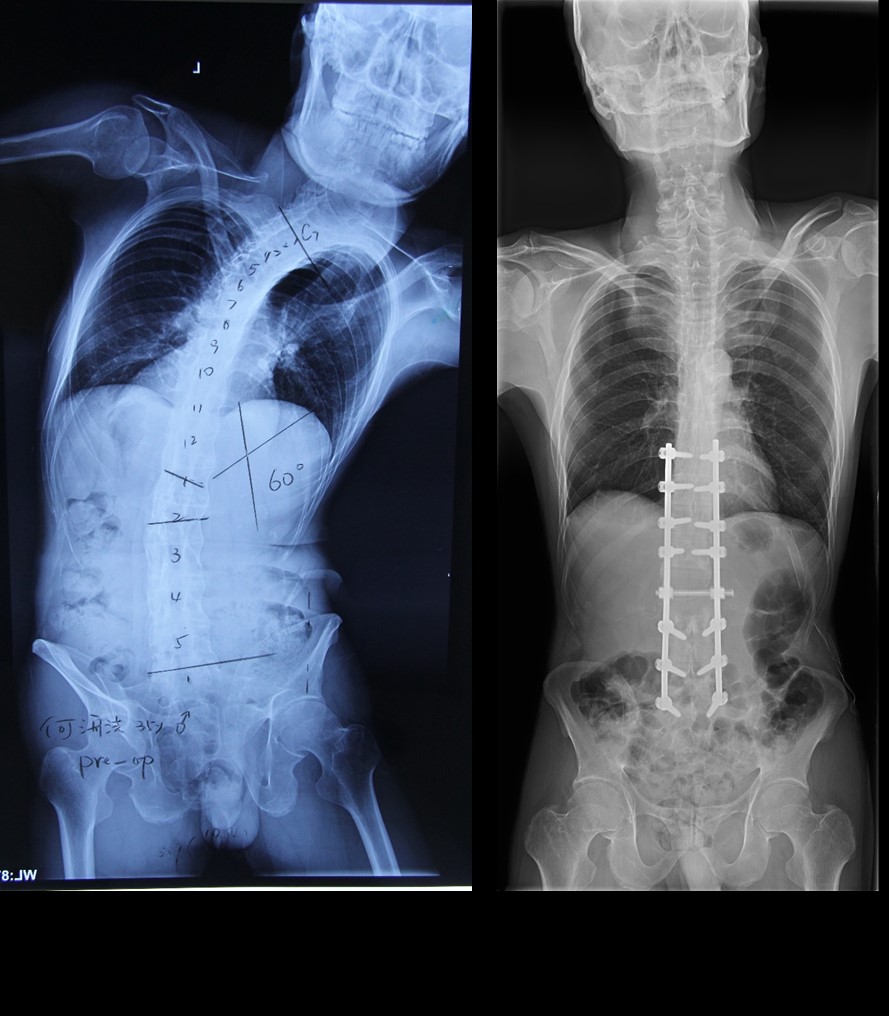

湘雅三医院骨科脊柱组专家李志跃副教授、张朝跃教授接待了何先生及其家属,详细了解病情后,组织科室骨干力量研究手术方案。本例患者畸形非常独特,不但有60°左右的后凸畸形,同时合并严重的侧凸与旋转畸形,手术难度更大。患者年龄轻,期望值较高,对手术效果提出了较高要求。湘雅三院骨科脊柱组的专家们已经多次利用3D打印技术帮助解决临床问题,积累了相当宝贵的经验。本次再度与华翔增量的工程师通力合作,对两种手术方案进行模拟演示,比较矫形效果。手术方案一:截骨节段选择腰3,优点是避开了脊髓圆锥,相对安全,缺点是矫形力度不够,无法矫正侧凸和旋转畸形。手术方案二:截骨节选择后凸和侧凸旋转最明显的腰1、2,做非对称的“V”形截骨,虽然一个半节段的差异,矫形优势却相当明显,既能矫正后凸畸形又能改变侧凸旋转畸形,缺点是截骨椎体量大,容易伤及脊髓圆锥,甚至导致不可逆转的下肢瘫痪,手术组的专家感受到空前的压力。

最终,湘雅三医院脊柱团队克服重重困难,顶住压力,采用了风险更大的矫形方案,选择在腰1、2节段行非对称的“V”形截骨。在华翔增量工程师制作的3D打印截骨导板帮助下,手术医生精确定位截骨椎体,截骨角度和深度和术前模拟完全吻合,整个截骨过程一气呵成。术前扭曲得像棵“歪脖子树”的何先生,术后第三天重新挺直了腰杆,在病房昂首阔步,引得病友们啧啧称奇。

据手术医生李志跃副教授介绍,相比依靠经验的传统截骨手术,利用3D打印截骨导板辅助的截骨手术优势明显,不但手术时间缩短,出血量大大减少,最重要的是截骨精度大大提高,术后矫形效果令医生和患者都非常满意。